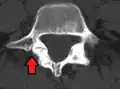

Anterolisthesis L5/S1. Blue arrow normal pars interarticularis. Red arrow is a break in pars interarticularis.

Isthmic anterolisthesis is where there is a defect in the pars interarticularis (spondylolysis).[15] It is the most common form of spondylolisthesis; also called spondylolytic spondylolisthesis, it occurs with a reported prevalence of 5–7 percent in the US population. A slip or fracture of the intravertebral joint is usually acquired between the ages of 6 and 16 years, but remains unnoticed until adulthood. Roughly 90 percent of these isthmic slips are low-grade (less than 50 percent slip) and 10 percent are high-grade (greater than 50 percent slip).[13] It is divided into three subtypes:[16]

- Isthmic anterolisthesis (also called type 2) is caused by a defect in the pars interarticularis (spondylolysis) but it can also be seen with an elongated pars.[11][12]